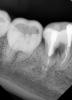

diesel87 Опубликовано 3 декабря, 2012 Поделиться Опубликовано 3 декабря, 2012 Вечер добрый, сегодня была пациентка, 36, 46 в обострение Pt обе, сделали снимки. это 46, тут разряжение по бифуркации, планирую на удаление это 36, не могу понять, есть ли тут тоже самое с бифуркацией, начал пытаться распломбировывать и проходить туда куда до меня не прошли, к сожалению времени оставалось всего минут 30 поэтому дошел только так, послезавтра отвели достаточно времени, попробуем пройти. Ссылка на комментарий

FBR Опубликовано 4 декабря, 2012 Поделиться Опубликовано 4 декабря, 2012 Вечер добрый, сегодня была пациентка, 36, 46 в обострение Pt обе, сделали снимки. это 46, тут разряжение по бифуркации, планирую на удаление это 36, не могу понять, есть ли тут тоже самое с бифуркацией, начал пытаться распломбировывать и проходить туда куда до меня не прошли, к сожалению времени оставалось всего минут 30 поэтому дошел только так, послезавтра отвели достаточно времени, попробуем пройти.Оба с пляжа... 1 Ссылка на комментарий